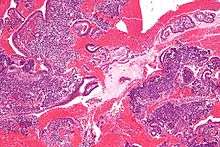

Endometrioid adenocarcinoma from biopsy. H&E stain.- Micrograph of the endometrium.